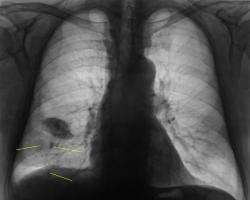

Флюорограмму расшифровывал врач того учреждения, откуда флюорограф, ну и рекомендацию "что сделать" - от туда. Но с учетом наличия синдрома "затемнения вне анатомических границ", конечно, лаборанты сделали и боковую, а уже только после этого пригласили "нашего" врача-рентгенолога "для принятия решения".

Повезло с лаборантами!.. Поскольку, помимо междолевого ограниченого плеврита, мне мерещатся еще очаги в легком, посоветую КТ

Я пока, это никак не трактую. Случай сегодняшний, думаю. Может коллеги, чего подскажут. Вот и последний срез. Подумываю, что в наличии и "базальный" выпот.